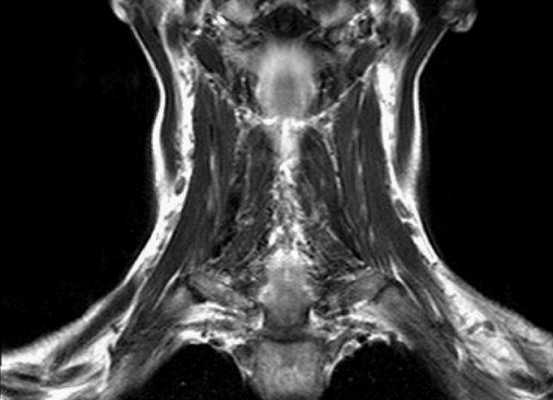

Результат МР-сканирования мягких тканей шеи

Для изучения строения кровеносной системы и диагностики онкологических патологий применяют магнитно-резонансную томографию с контрастным усилением. В качестве «окрашивающего» препарата используют раствор хелатов гадолиния. Вещество характеризуется низкой токсичностью и гипоаллергенностью. Контраст выводится из организма печенью и почками, время полного очищения составляет 24-72 часа.

Магнитно-резонансная томография тазового пояса

МРТ мягких тканей шеи назначают при наличии следующих симптомов: